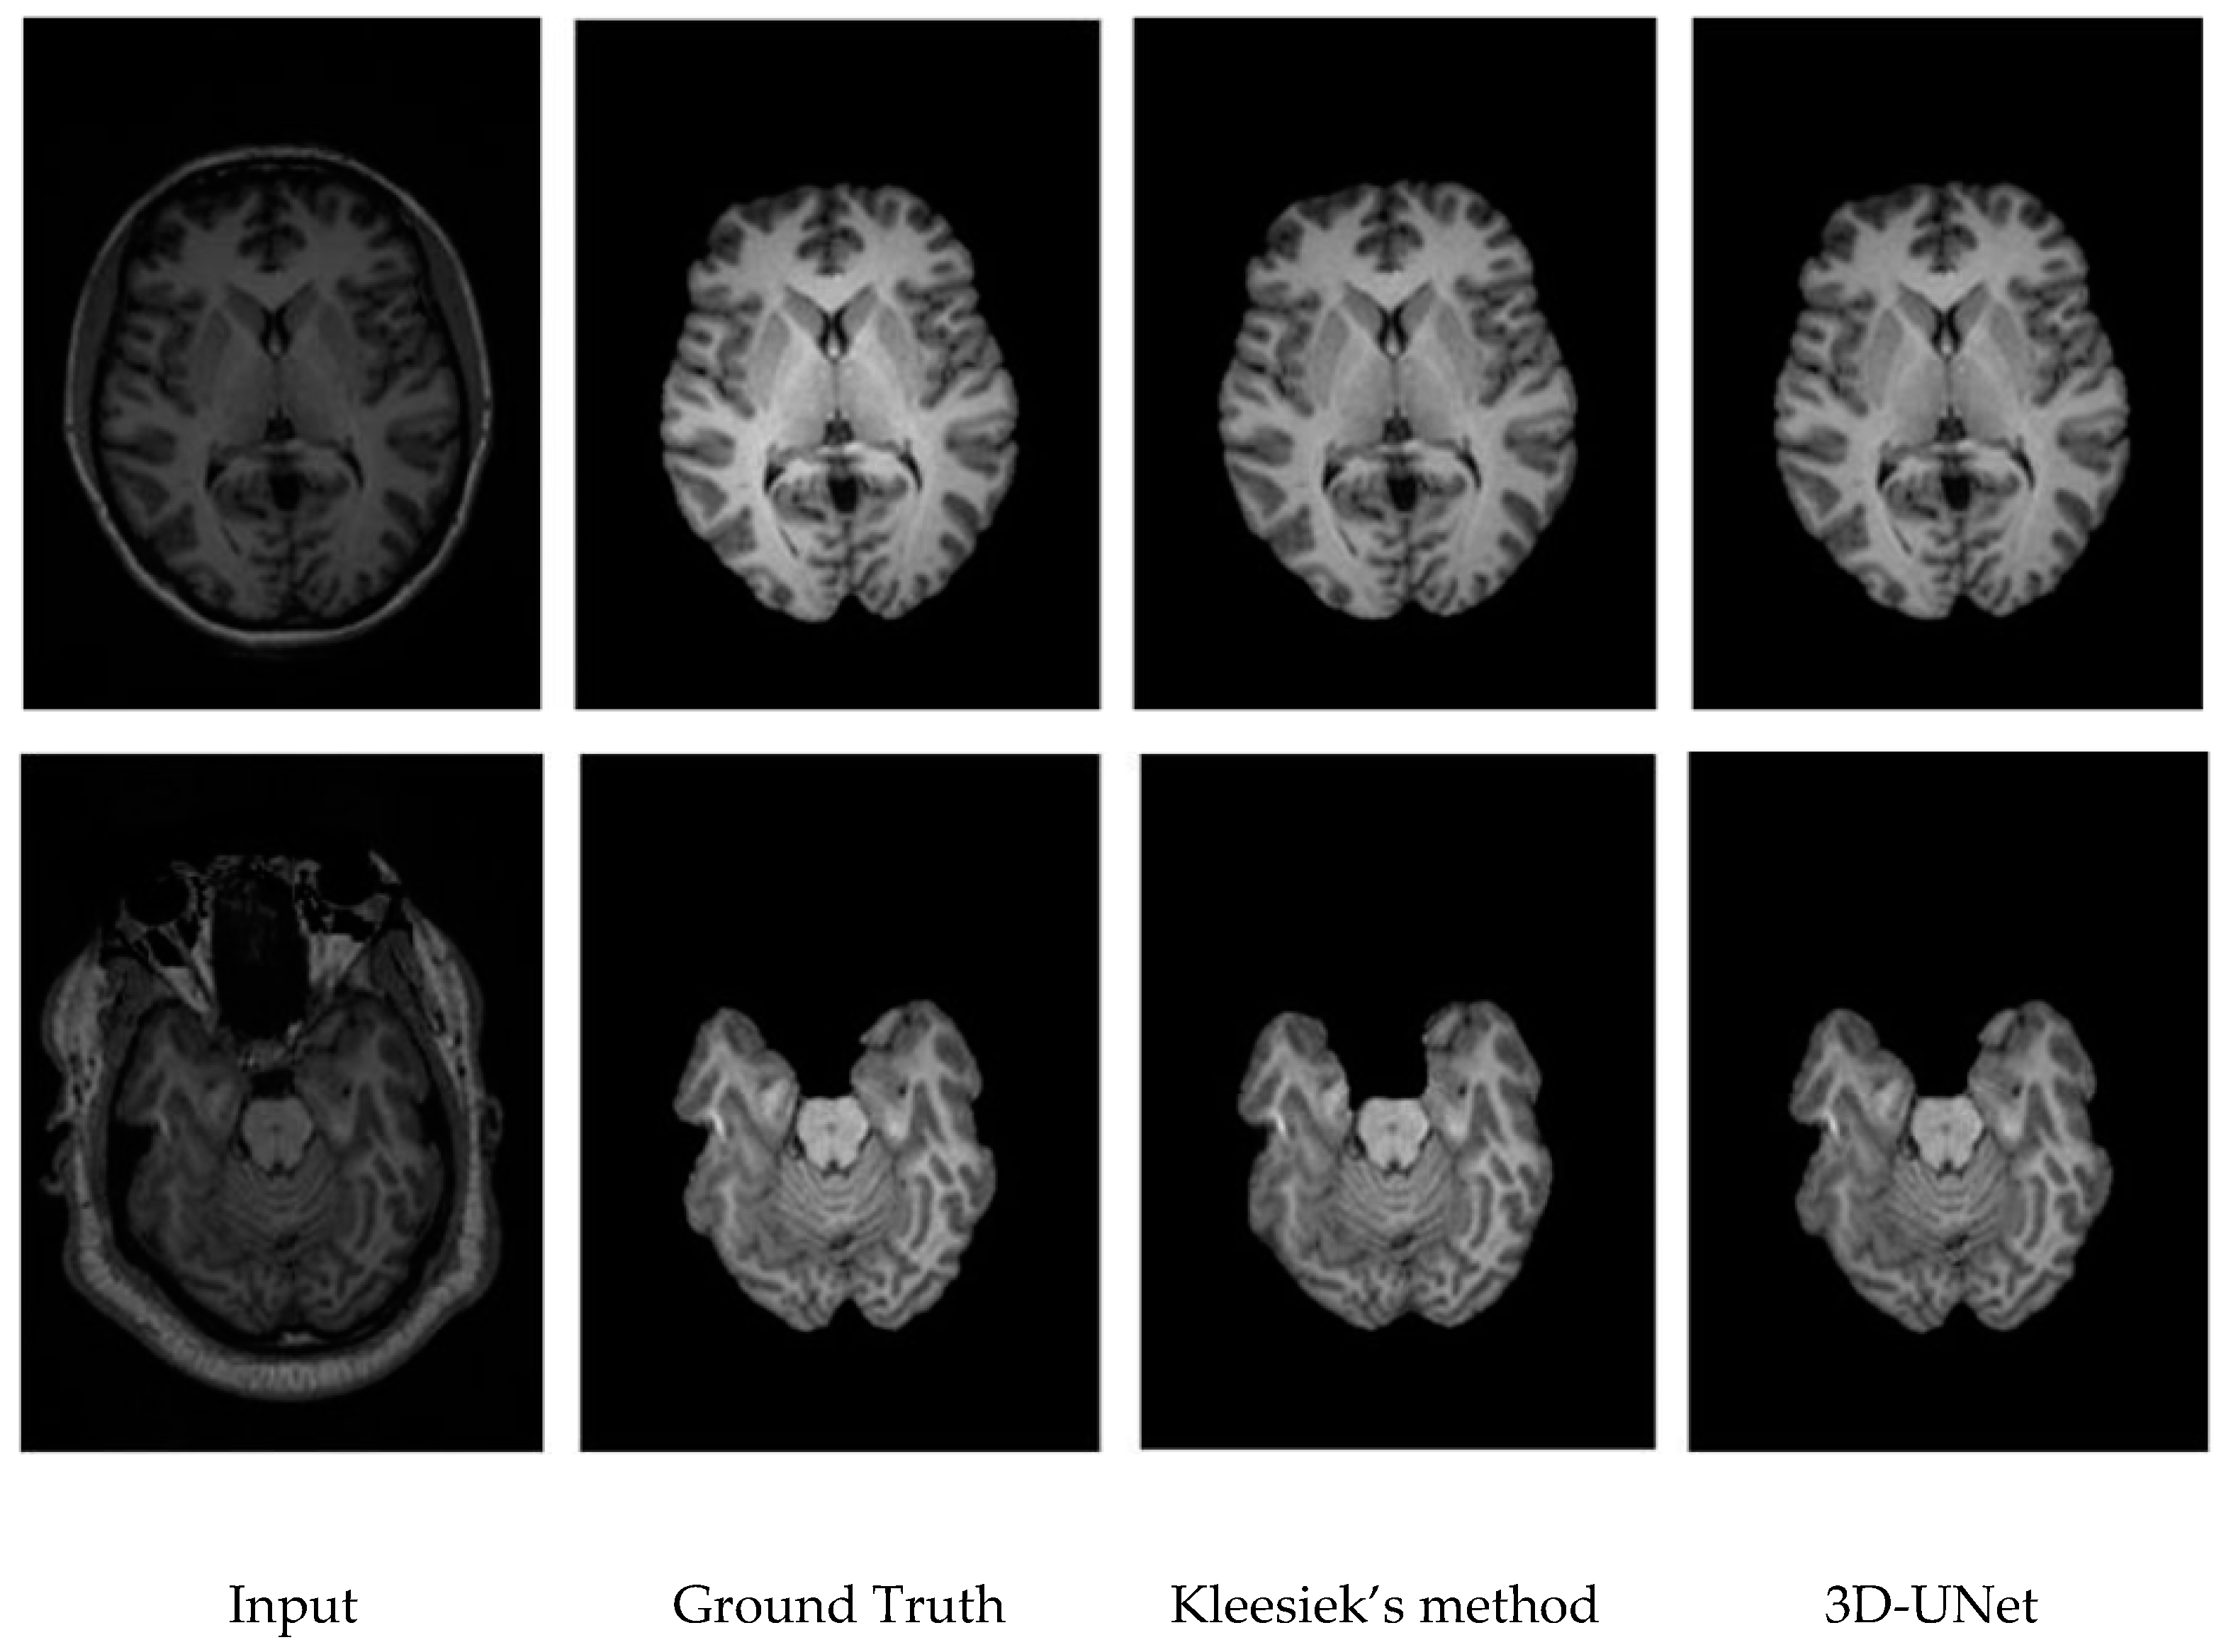

3.3. Qualitative Results.